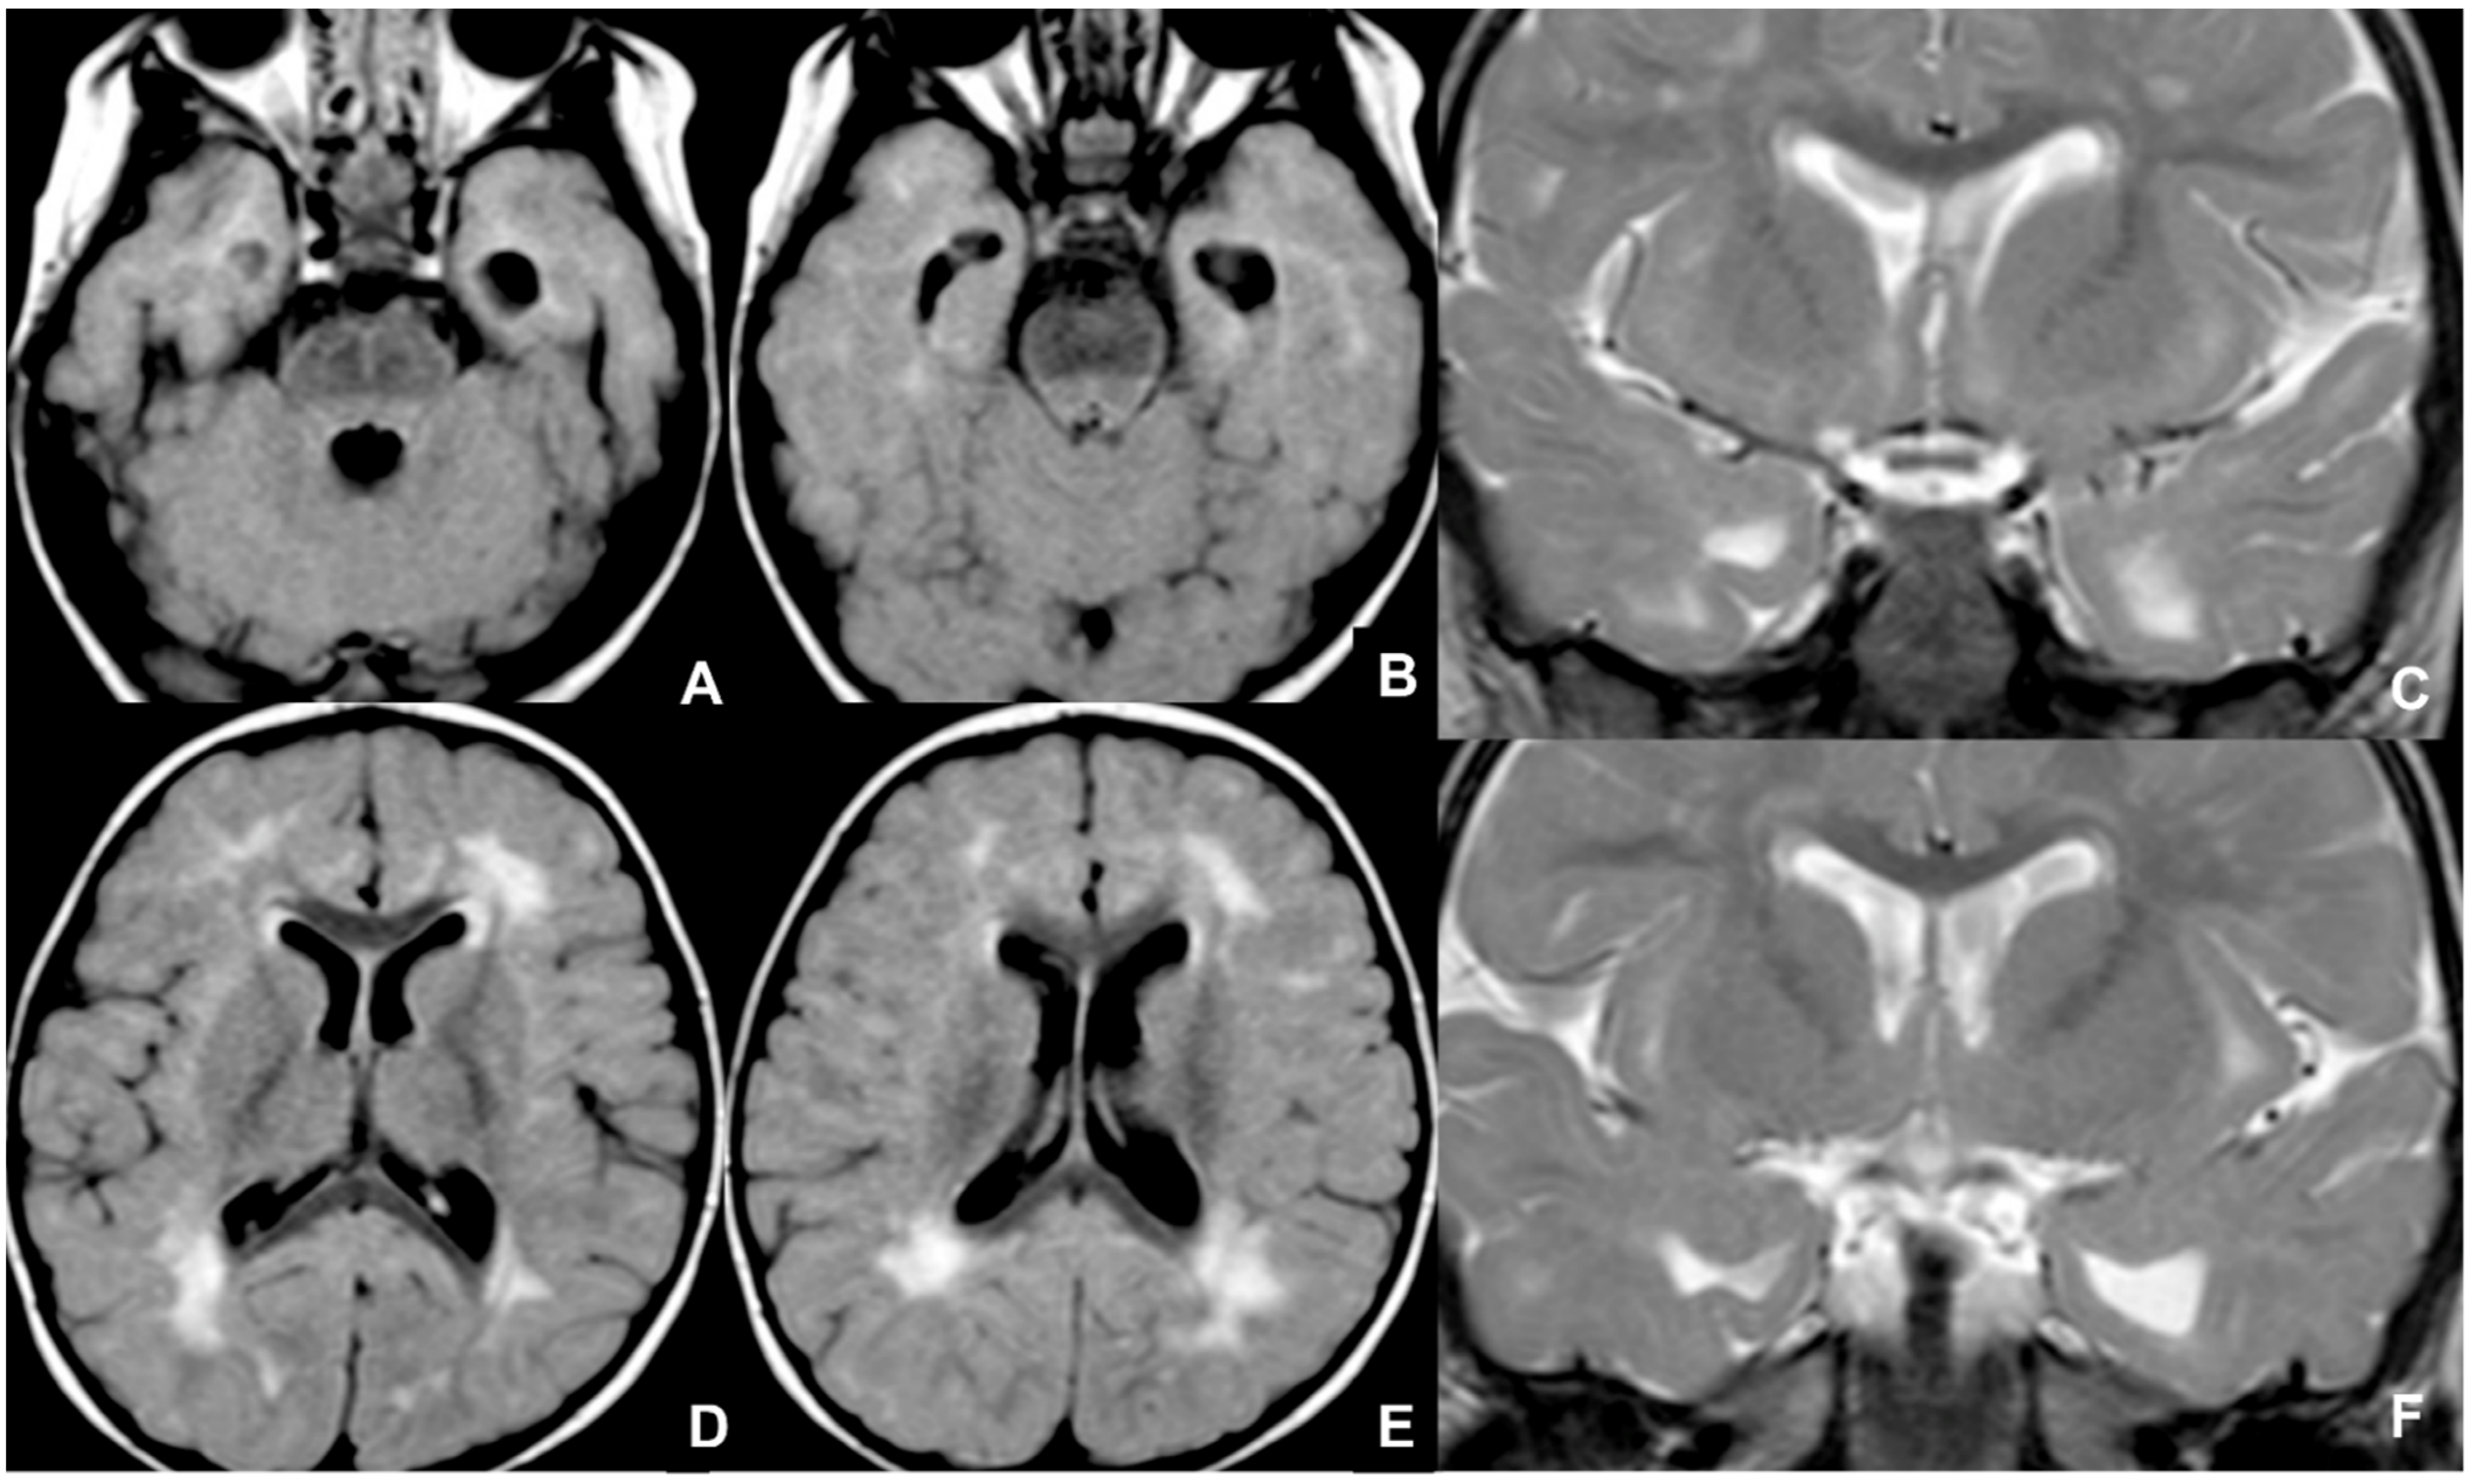

2.4. Herpes Simplex

- Baskin, H.J.; Hedlund, G. Neuroimaging of herpesvirus infections in children. Pediatr. Radiol. 2007, 37, 949–963. [Google Scholar] [CrossRef]

- Kubota, T.; Ito, M.; Maruyama, K.; Kato, Y.; Miyajima, Y.; Ogawa, A.; Kuno, K.; Okumura, A.; Watanabe, K. Serial diffusion-weighted imaging of neonatal herpes encephalitis: A case report. Brain Dev. 2007, 29, 171–173. [Google Scholar] [CrossRef]

- Okanishi, T.; Yamamoto, H.; Hosokawa, T.; Ando, N.; Nagayama, Y.; Hashimoto, Y.; Maihara, T.; Goto, T.; Kubota, T.; Kawaguchi, C.; et al. Diffusion-weighted MRI for early diagnosis of neonatal herpes simplex encephalitis. Brain Dev. 2015, 37, 423–431. [Google Scholar] [CrossRef]

- Wong, A.M.; Yeh, C.H.; Lin, J.J.; Liu, H.L.; Chou, I.J.; Lin, K.L.; Wang, H.S. Arterial spin-labeling perfusion imaging of childhood encephalitis: Correlation with seizure and clinical outcome. Neuroradiology 2018, 60, 961–970. [Google Scholar] [CrossRef]

- Soares, B.P.; Provenzale, J.M. Imaging of Herpesvirus Infections of the CNS. AJR Am. J. Roentgenol. 2016, 206, 39–48. [Google Scholar] [CrossRef]